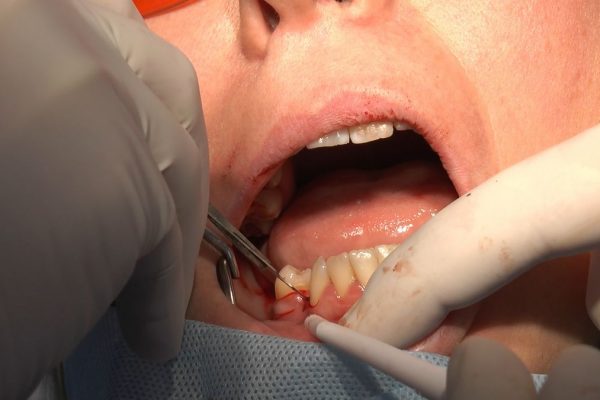

W ostatni weekend czerwca 2018 roku kursanci II Sezonu Preludium Implantologii odbyli piątą, finałową sesję, która w całości podporządkowana była praktyce. W ciągu dwóch dni zabiegowych Lekarze uczestniczący w szkoleniu przeprowadzili szereg zabiegów pod kierunkiem dr n.med. Violetty Szycik. Wszczepili 17 implantów oraz przeprowadzili ekstrakcje i zabiegi regeneracyjne kości. Zabiegi były wykonywane także w sedacji dożylnej z udziałem specjalisty anestezjologii i intensywnej terapii dr Jolanty Grzybowskiej. Preludium implantologii to nowy program edukacyjny dla adeptów implantologii stomatologicznej, którego celem jest wprowadzenie do implantologii poprzez pozyskanie wiedzy w szerokim zakresie i uwzględnieniem szczegółów mających decydujące znaczenie dla powodzenia leczenia implantologicznego. Ale tak jak wszystkie szkolenia w Instytucie Vivadental, w tym wiodące Practiculum Implantologii, zorientowane jest na praktyce i samodzielnym wykonywaniu zabiegów pod kierunkiem Mentora. To najlepsza edukacja w medycynie zabiegowej, a zarazem najlepszy start do implantologii.